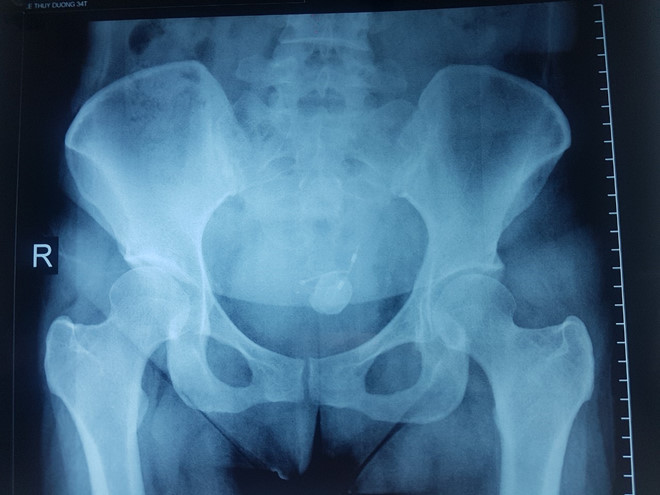

| Nhìn kết quả chụp X-quang thấy vòng tránh thai đi "nhầm" chỗ |

Chị D. đến Bệnh viện Hoàn Mỹ Vạn Phúc 2 trong tình trạng tiểu khó (tiểu buốt, tiểu rắt), đau bụng vùng hạ vị. Qua thăm khám kết hợp siêu âm, chụp phim X-quang, bác sĩ chẩn đoán sỏi bàng quang khoảng 2,2 cm, vùng bàng quang bao quanh một nhánh chữ T của vòng tránh thai (nhánh chữ T đâm xuyên thành bàng quang), một phần của vòng chữ T nằm trong ổ bụng.